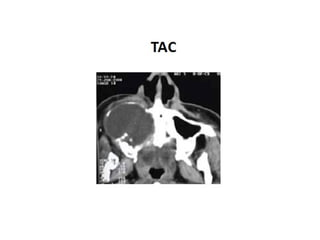

TAC TUMOR PAROTIDA IZQ.